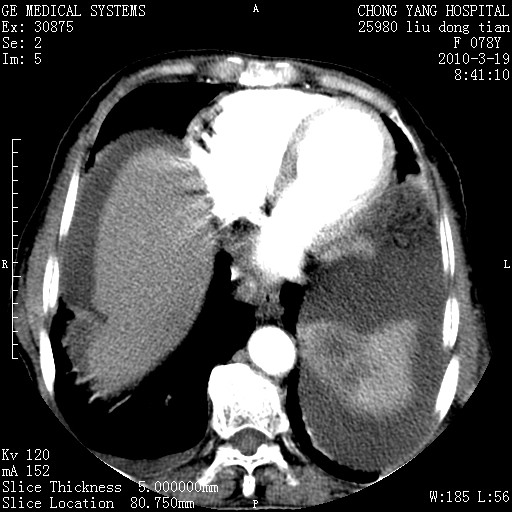

胰头有肿块形成,胰头ca伴肝脾、腹膜腹膜后转移

分开来讲:肝左叶、尾叶病灶有不均强化像肝癌;

脾脏病灶无强化,像多发囊肿或淋巴管瘤,不除外淋巴瘤(低强化);

肝门、胰腺头、腹膜后多个团块: 淋巴瘤,转移;

一元论最好了 淋巴瘤所致改变; 胆囊癌转移不像,胆囊周围肝组织清晰,肝癌淋巴结转移?三元论都不止。

胰头ca伴肝脾、腹膜腹膜后转移!

最后报的胰头癌多发转移,脾脏单独考虑囊肿或淋巴管瘤。